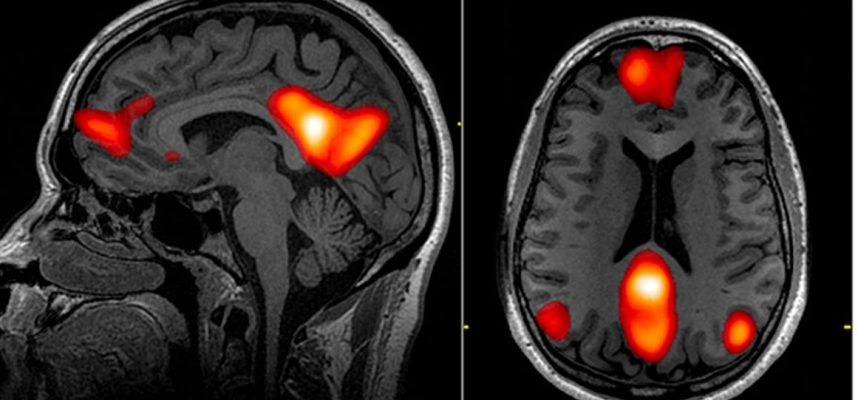

Za povzetek nekaterih hitro kopičenih podatkov sta dva nevrologa pregledala študije, ki so preučevale, kako COVID-19 moti vzorce normalne možganske funkcije, ki jih je mogoče izmeriti z EEG.

EEG, okrajšava za elektroencefalogram, beleži električno aktivnost v različnih delih možganov osebe, običajno z uporabo elektrod, nameščenih na lasišču.

EEG pregledi bolnikov so pokazali vrsto nepravilnosti v možganski aktivnosti, vključno z nekaterimi ritmičnimi vzorci in epileptičnimi izbruhi aktivnosti. Najpogostejša opažena nenormalnost je bilo razpršeno upočasnitev, to je splošno upočasnitev možganskih valov, kar kaže na splošno disfunkcijo možganske aktivnosti.

Glede na lokalizirane učinke so tretjino vseh ugotovljenih nepravilnosti našli v čelnem režnju, delu možganov, ki izvaja izvršilne miselne naloge, kot sta sklepanje in odločanje. Tudi čelni reženj nam pomaga uravnavati svoja čustva, nadzorovati vedenje in je vključen v učenje in pozornost.

“Ti podatki nam govorijo, da moramo preizkusiti EEG pri širšem krogu bolnikov, pa tudi druge vrste slikanja možganov, kot sta MRI ali CT, ki nam bodo omogočili, da si bomo podrobneje ogledali čelni reženj,” je povedal nevrolog in soavtor študije Zulfi Hanif. z medicinske fakultete Baylor v Houstonu.